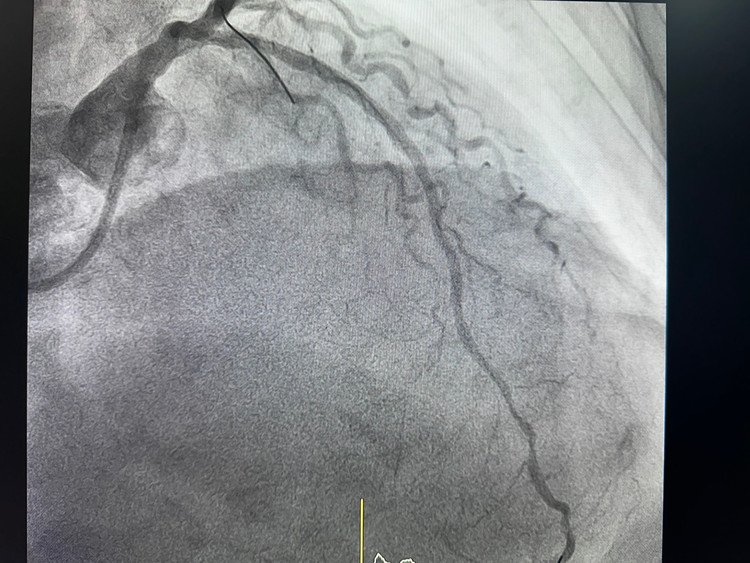

| Huyết khối trên phim chụp - ảnh BVCC |

Tiên lượng đây là trường hợp rất nặng nguy hiểm đến tính mạng, bệnh nhân nhanh chóng được chuyển vào Trung tâm tim mạch điện quang can thiệp cấp cứu. Chụp động mạch vành qua da có hình ảnh: Xơ vữa gây hẹp tắc cấp tính hoàn toàn LAD (o), xơ vữa gây hẹp 40% RCA (p), 50% RCA(m).